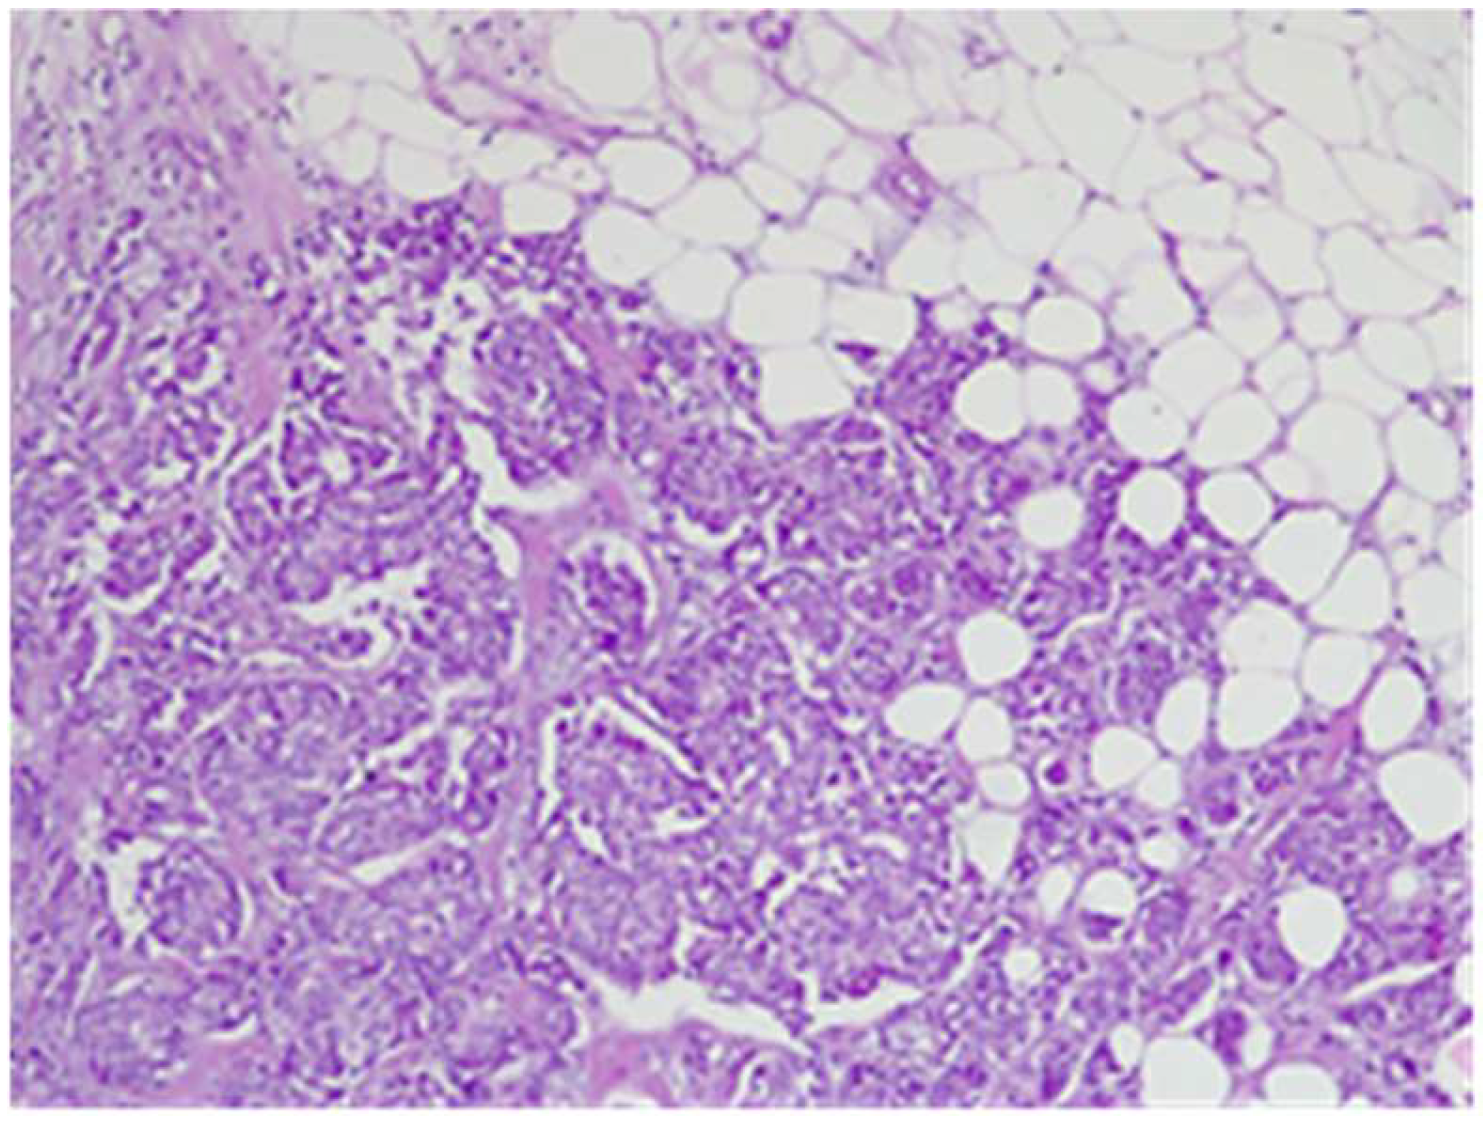

2. Case Report